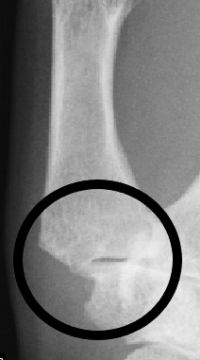

Die schmerzhafte Verschleißbildung des Daumensattelgelenkes bedeutet häufig eine erhebliche Beeinträchtigung der gesamten betroffenen Hand. Bei jedem Zugreifen wird der Daumen als Gegenpart der übrigen Finger benötigt; ist er eingeschränkt, kommt es zur Einschränkung der Greiffunktion bis hin zum Funktionsverlust. Nach Ausreizen der konservativen Behandlungsmöglichkeiten kommt hier ein operatives Verfahren zur dauerhaften Schmerzreduktion bei guter Beweglichkeit zum Tragen.

Dabei werden die abgenutzten Gelenkflächen des Daumensattelgelenkes entfernt. Der Daumenstrahl wird über eine Sehnenverbindung in seiner Position gehalten. Postoperativ erfolgt die Nachbehandlung zunächst über eine Schienenruhigstellung. Nach 4-6 W ist das Gewebe belastungsstabil verheilt und der Daumen kann beübt werden. Das schmerzhafte Gelenkgewebe ist dauerhaft entfernt, die Beweglichkeit bleibt erhalten.